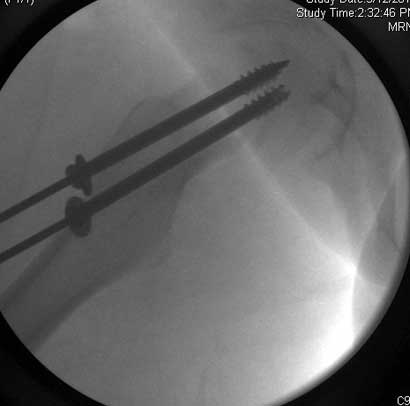

Severe slip treated with arthroscopic Dunn type of femoral neck osteotomy

Severe slip treated with arthroscopic Dunn type of femoral neck osteotomy, reduction and fixation.